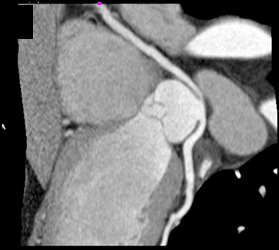

Anomalous RCA Off Lca